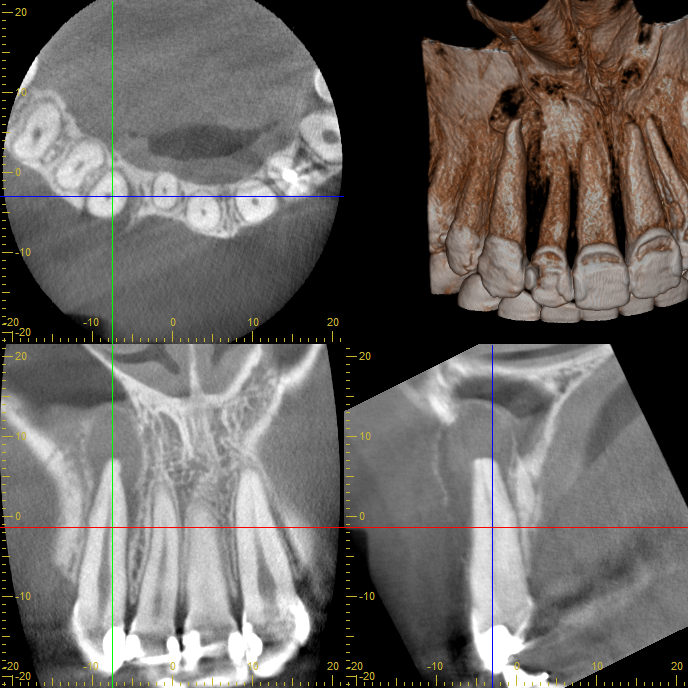

CTで確認すると、根の先には大きな嚢胞(うみの袋)が見られました。

しかし、感染源を丁寧に除去することで歯を残せる可能性があると判断。

CT画像を詳細に確認した結果、根尖部の嚢胞は大きいものの、根の構造はしっかり保たれており、保存の可能性があると判断しました。

そのため、外科手術ではなくマイクロスコープ下での精密根管治療を選択しました。